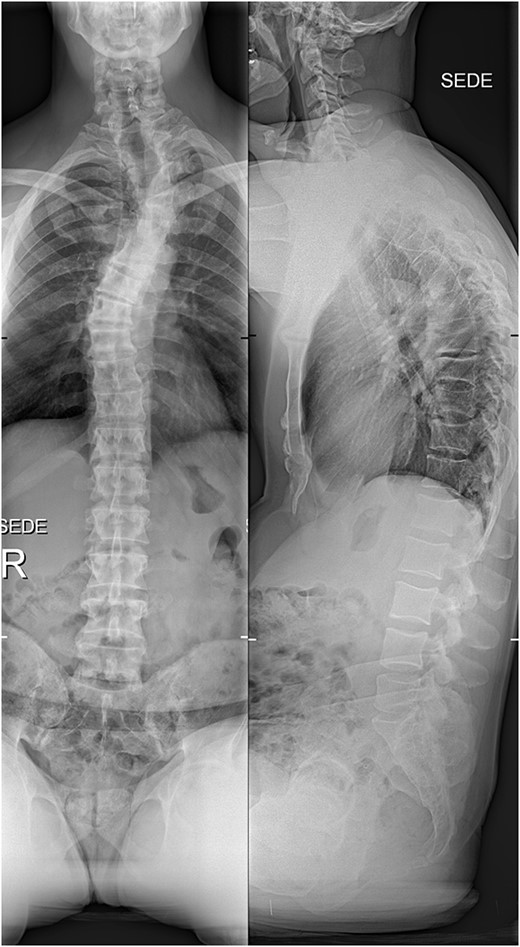

X-rays at the final follow-up 4 years after the surgery. Anteroposterior view (left) and lateral view (right).

Six weeks after surgery he was transferred to a tertiary rehabilitation center, ambulating using a walker, but remained wheelchair-bound for longer distances. The postoperative pain was manageable with non-opioids. During the regular follow-ups, the paraplegia with severe spasticity persisted, without significant pain. A subsequent insertion of the intrathecal baclofen pump in a tertiary rehabilitation facility enabled the patient to manage the muscle spasms in his lower limbs, particularly during transfers from the wheelchair to bed and vice versa. The patient was able to urinate spontaneously with minimal urine retention, and no need for self-catheterisation, reporting satisfaction with the outcome of the surgery and rehabilitation, which enabled him a return to his workplace and retain a significant level of independence in everyday activities. On the final follow-up imaging, 4 years after the surgery, no significant deformity progression and no evidence of neurologic impairment were observed (Figs 4 and 5).